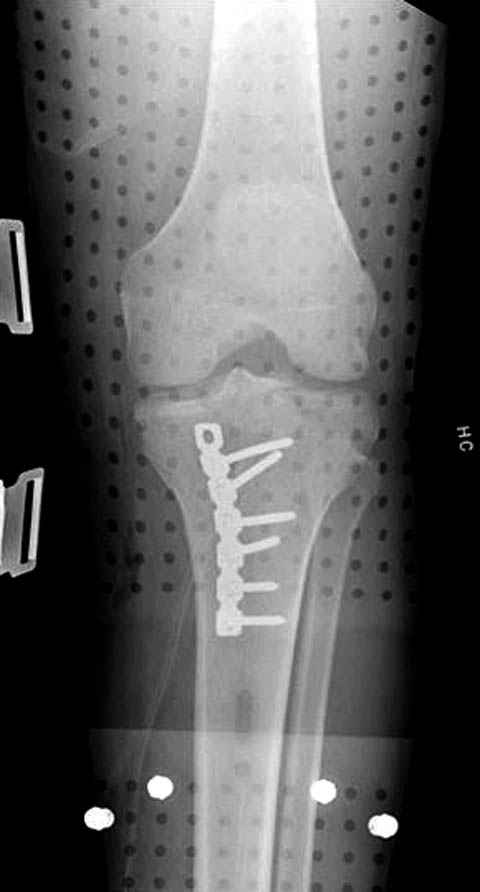

Уважаемые коллеги! В прошлую пятницу больной прооперирован - как и планировалось мыщелковая LCP от ChM. Малоинвазивно не получилось - один большой доступ :(. (но с минимальным скелетированием б/б кости). Наружный мыщелок собрали, но по контролю видно, что задне-медиальный отдел метаэпифиза смещен. Фиксировать не стали (?). 4-е сутки после операции - по м/тканям без проблем. Дополнительная иммобилизация синтетическим тутором.

Интересно услышать ваши мнения, анализ ошибок...

P. S. перелом диафиза на контроле не совсем захвачен, но проблем там нет. Приношу извинения за низкое качество Р-грамм - выполнены на сканере (фотоаппарат не работает :)) .

Трудно поверить, что разрекламированная Ортопедическая школа Восточной Украины позволяет такие странные снимки? На прямом снимке сохранен общий контур плато, но не известна судьба импрессии суставной поверхности. На полубоковой?, оставлен без репозиции задне-медиальный отдел, и навряд ли после такой фиксации можно удовлетвориться результатом.

Такая ситуация характерна для многих, когда принимается ошибочное решение, т.е пытаются фиксировать одним имплантом переломы двух мыщелков. Латеральная пластина приемлема только для тех случаев, когда сохраняется интактным медиальный диафизарный кортекс и отсутствует фрагментация на верхушке медиального перелома.